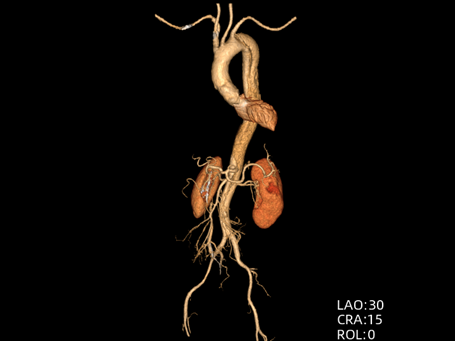

B型夹层:药物与介入治疗

主动脉腔内修复术:微创治疗。通过大腿根部的股动脉,将一个覆膜支架送入主动脉夹层部位,像打补丁一样覆盖住内膜破口,使血流不再进入假腔,促进假腔血栓化愈合。